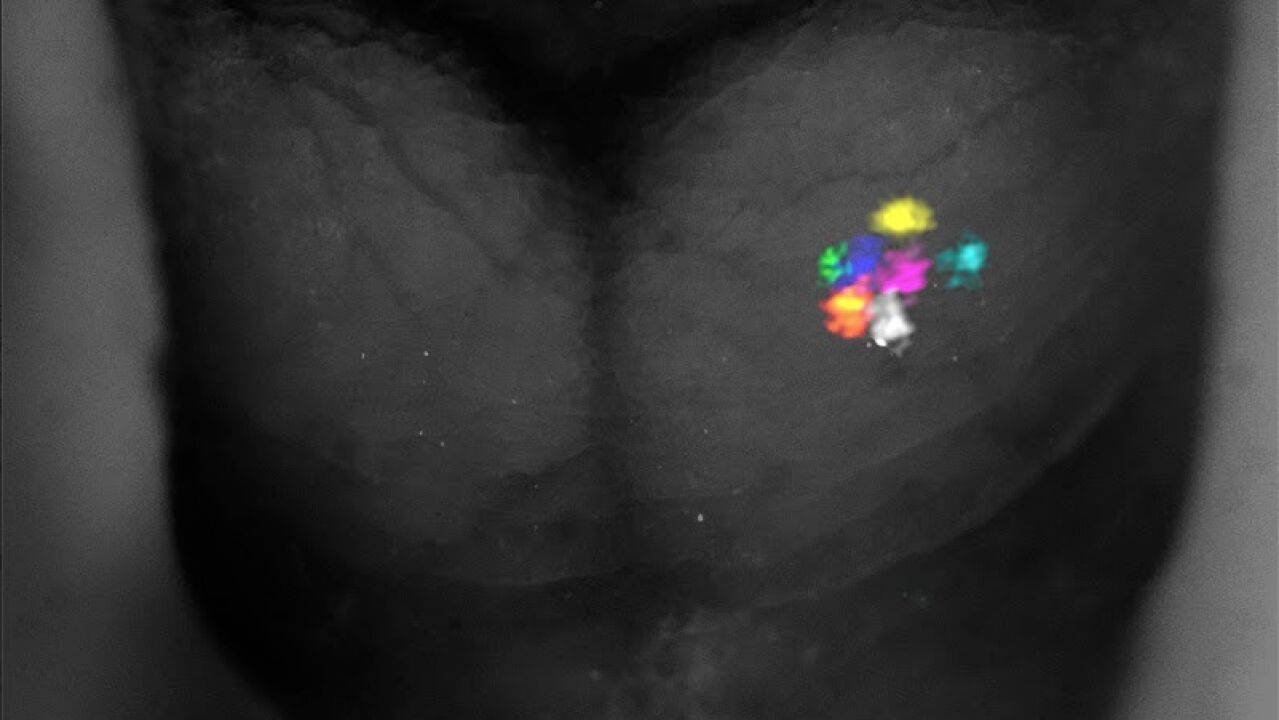

Mapa sensorial que representa cómo el cerebro de un embrión de ratón organiza las sensaciones faciales antes del nacimiento. | IN CSIC-UMH

La científica Mar Aníbal, primera autora del artículo publicado, ha explicado que “nos centramos en el mapa sensorial de la cara del ratón, ya que para estos animales la cara es tan crucial como las manos para los humanos”. Ha añadido que se observó que, en ausencia de los bigotes principales, la región del cerebro que normalmente procesa esa información desaparece casi por completo y la región de los bigotes del labio superior, que son más pequeños, numerosos y con funciones secundarias en el procesamiento táctil, se expande para ocupar su territorio. Este proceso ocurre solo si la pérdida sensorial se da antes del nacimiento.